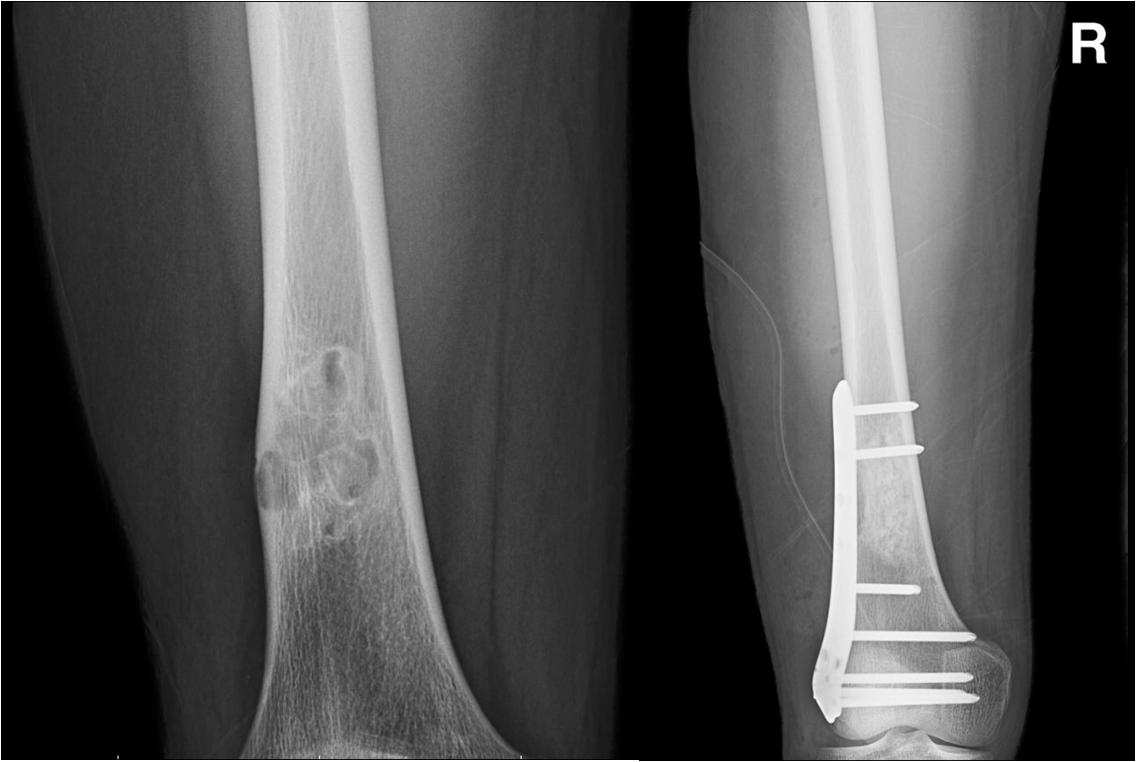

恶性骨肉瘤!大范围浸润!骨科团队精准医治!

良性骨肿瘤—胫骨下段骨囊肿x线表现(图)